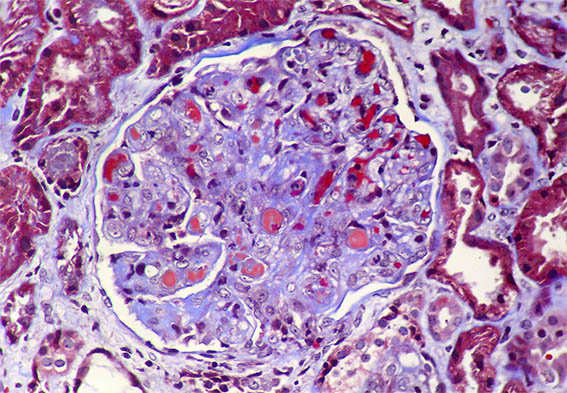

Figure 3. Masson´s trichrome stain, X400. Identify intracapillary hyaline material (misnamed "hyaline thrombi").